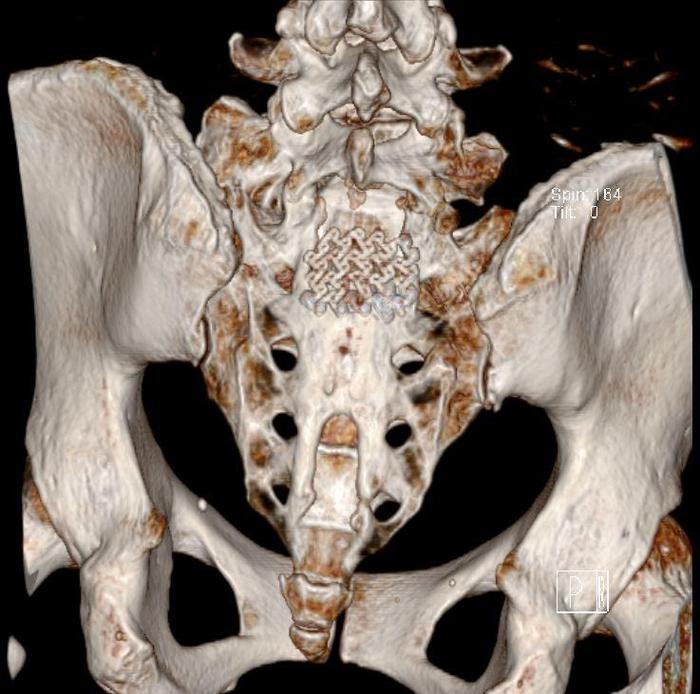

中年女性,骶管小囊肿,当地医院2年前手术,术后症状加重,骶尾臀部剧烈疼痛,VAS 7分,不能站、立、行超过15分钟,术后至今每天服用止痛药。从影像来看,骶管囊肿并不大,为何术后疼痛这么明显呢?应该怎么处理呢

术中:1. 骶管囊肿虽然很小,但漏口很大;予以严密的封堵;2. 由于初次手术未修补骶骨骨窗,所以患者不能久站,本次手术用钛板修复骨窗,重建一个骨性的压力屏障。